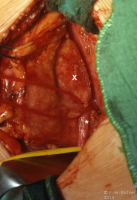

Bei dem 8-jährigen Jungen waren Schmerzen im linken Oberbauch sowie rezidivierende Harnwegsinfekte Ursachen für die Abklärung. sonographisch und röntgenologisch fanden sich Nierenkelchkonkremente in einer Harnstaaungsniere (Abbildungen 21,22,23). Bei der retrograden Sondierung ergab sich ein deutlicher Widerstand in Höhe des Ureterabgangs. Die Freilegung zeigte eine aberrierende Arterie als Abflusshindernis. Nach Durchtrennung des Harnleiters Eröffnung des Nierenbeckens zur Steinentfernung und Abgangsplastik des vorgelagerten Harnleiters. Normalisierung der Abflussverhältnisse.